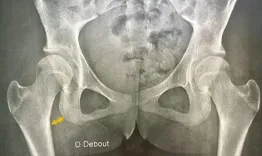

3 patients with borderline hips - conservative or recon?

The distinction between conservative surgery (PAO or arthroscopy) and non-conservative treatments has evolved significantly with the development of modern decision-making algorithms.

Live clinics: Hips- Indication limit. 3 patients with borderline hips- conservative or recon?

Nicolas Bonin, Kristoff Corten, Frédéric Laude, Nicolas Reina